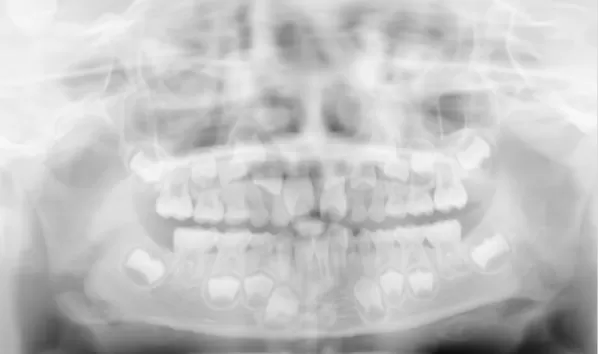

X-rays before treatment

[Panoramic Radiography/Lateral Cephalogram]